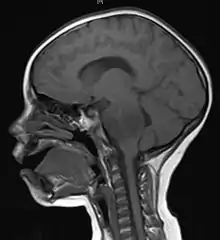

Cell phones are known to generate electromagnetic fields (EMFs). This is how they communicate with cell towers and why we can communicate almost everywhere. The problem is that phones emit these electromagnetic waves in all directions, including into our bodies. A 1996 study explored the Specific Absorption Rate (SAR), the rate of energy absorption, in models of a human adult brain, a 10 year old brain, and a 5 year old brain during cell phone use. Their study showed notably higher SAR's in a 10 year old than an adult, and even higher SAR's in a 5 year old. These results prove that EMFs penetrate deeper into children’s brains than adults’ brains[14] and contribute to the idea that cell phones may be more harmful to children than to adults. This increased susceptibility to EMF penetration is attributed to the fact that children have smaller brains and softer brain tissue than adults[15].